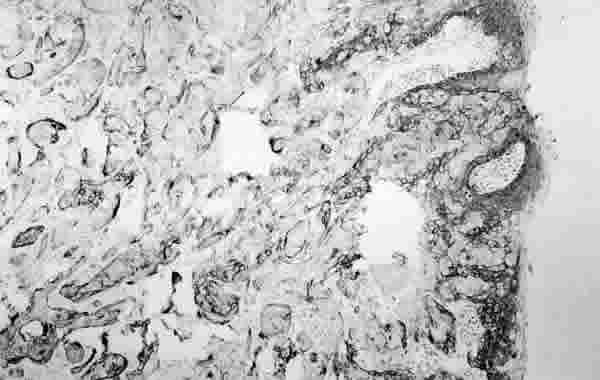

Figura 4

INMUNOPOSITIVIDAD PARA EL ANTÍGENO DE MEMBRANA EPITELIAL. AL IGUAL QUE CON LA CITOQUERATINA OBSÉRVESE CÓMO LAS CÉLULAS TUMORALES Y EL EPITELIO NORMAL SE TIÑEN DE OSCURO, QUE CORRESPONDE A LA TINCIÓN MARRÓN CON PEROXIDASA (PEROXIDASA).